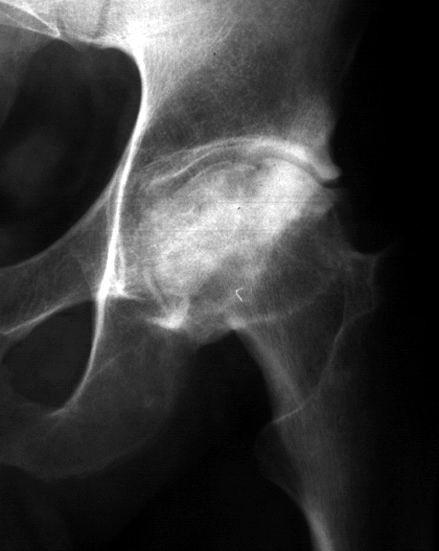

COLAPSO AFECTA LA SUPF SUBCONDRAL PERDIENDO SU MORFOLOGIA NORMAL

LA INCONGRUENCIA ARTICULAR PRODUCE PERDIDA DEL GROSOR DEL CARTILAGO Y CAMBIOS EN EL ACETABULO